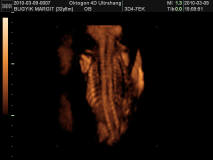

Megvolt az Uh és doktornő uh-on megint rendben talált mindent. Olyan kis édes volt. Kivételesen aludt, felébredt, elaludt. Nem volt akkora ugra-bugra most.

Kitaláljátok a nemét? :lol: